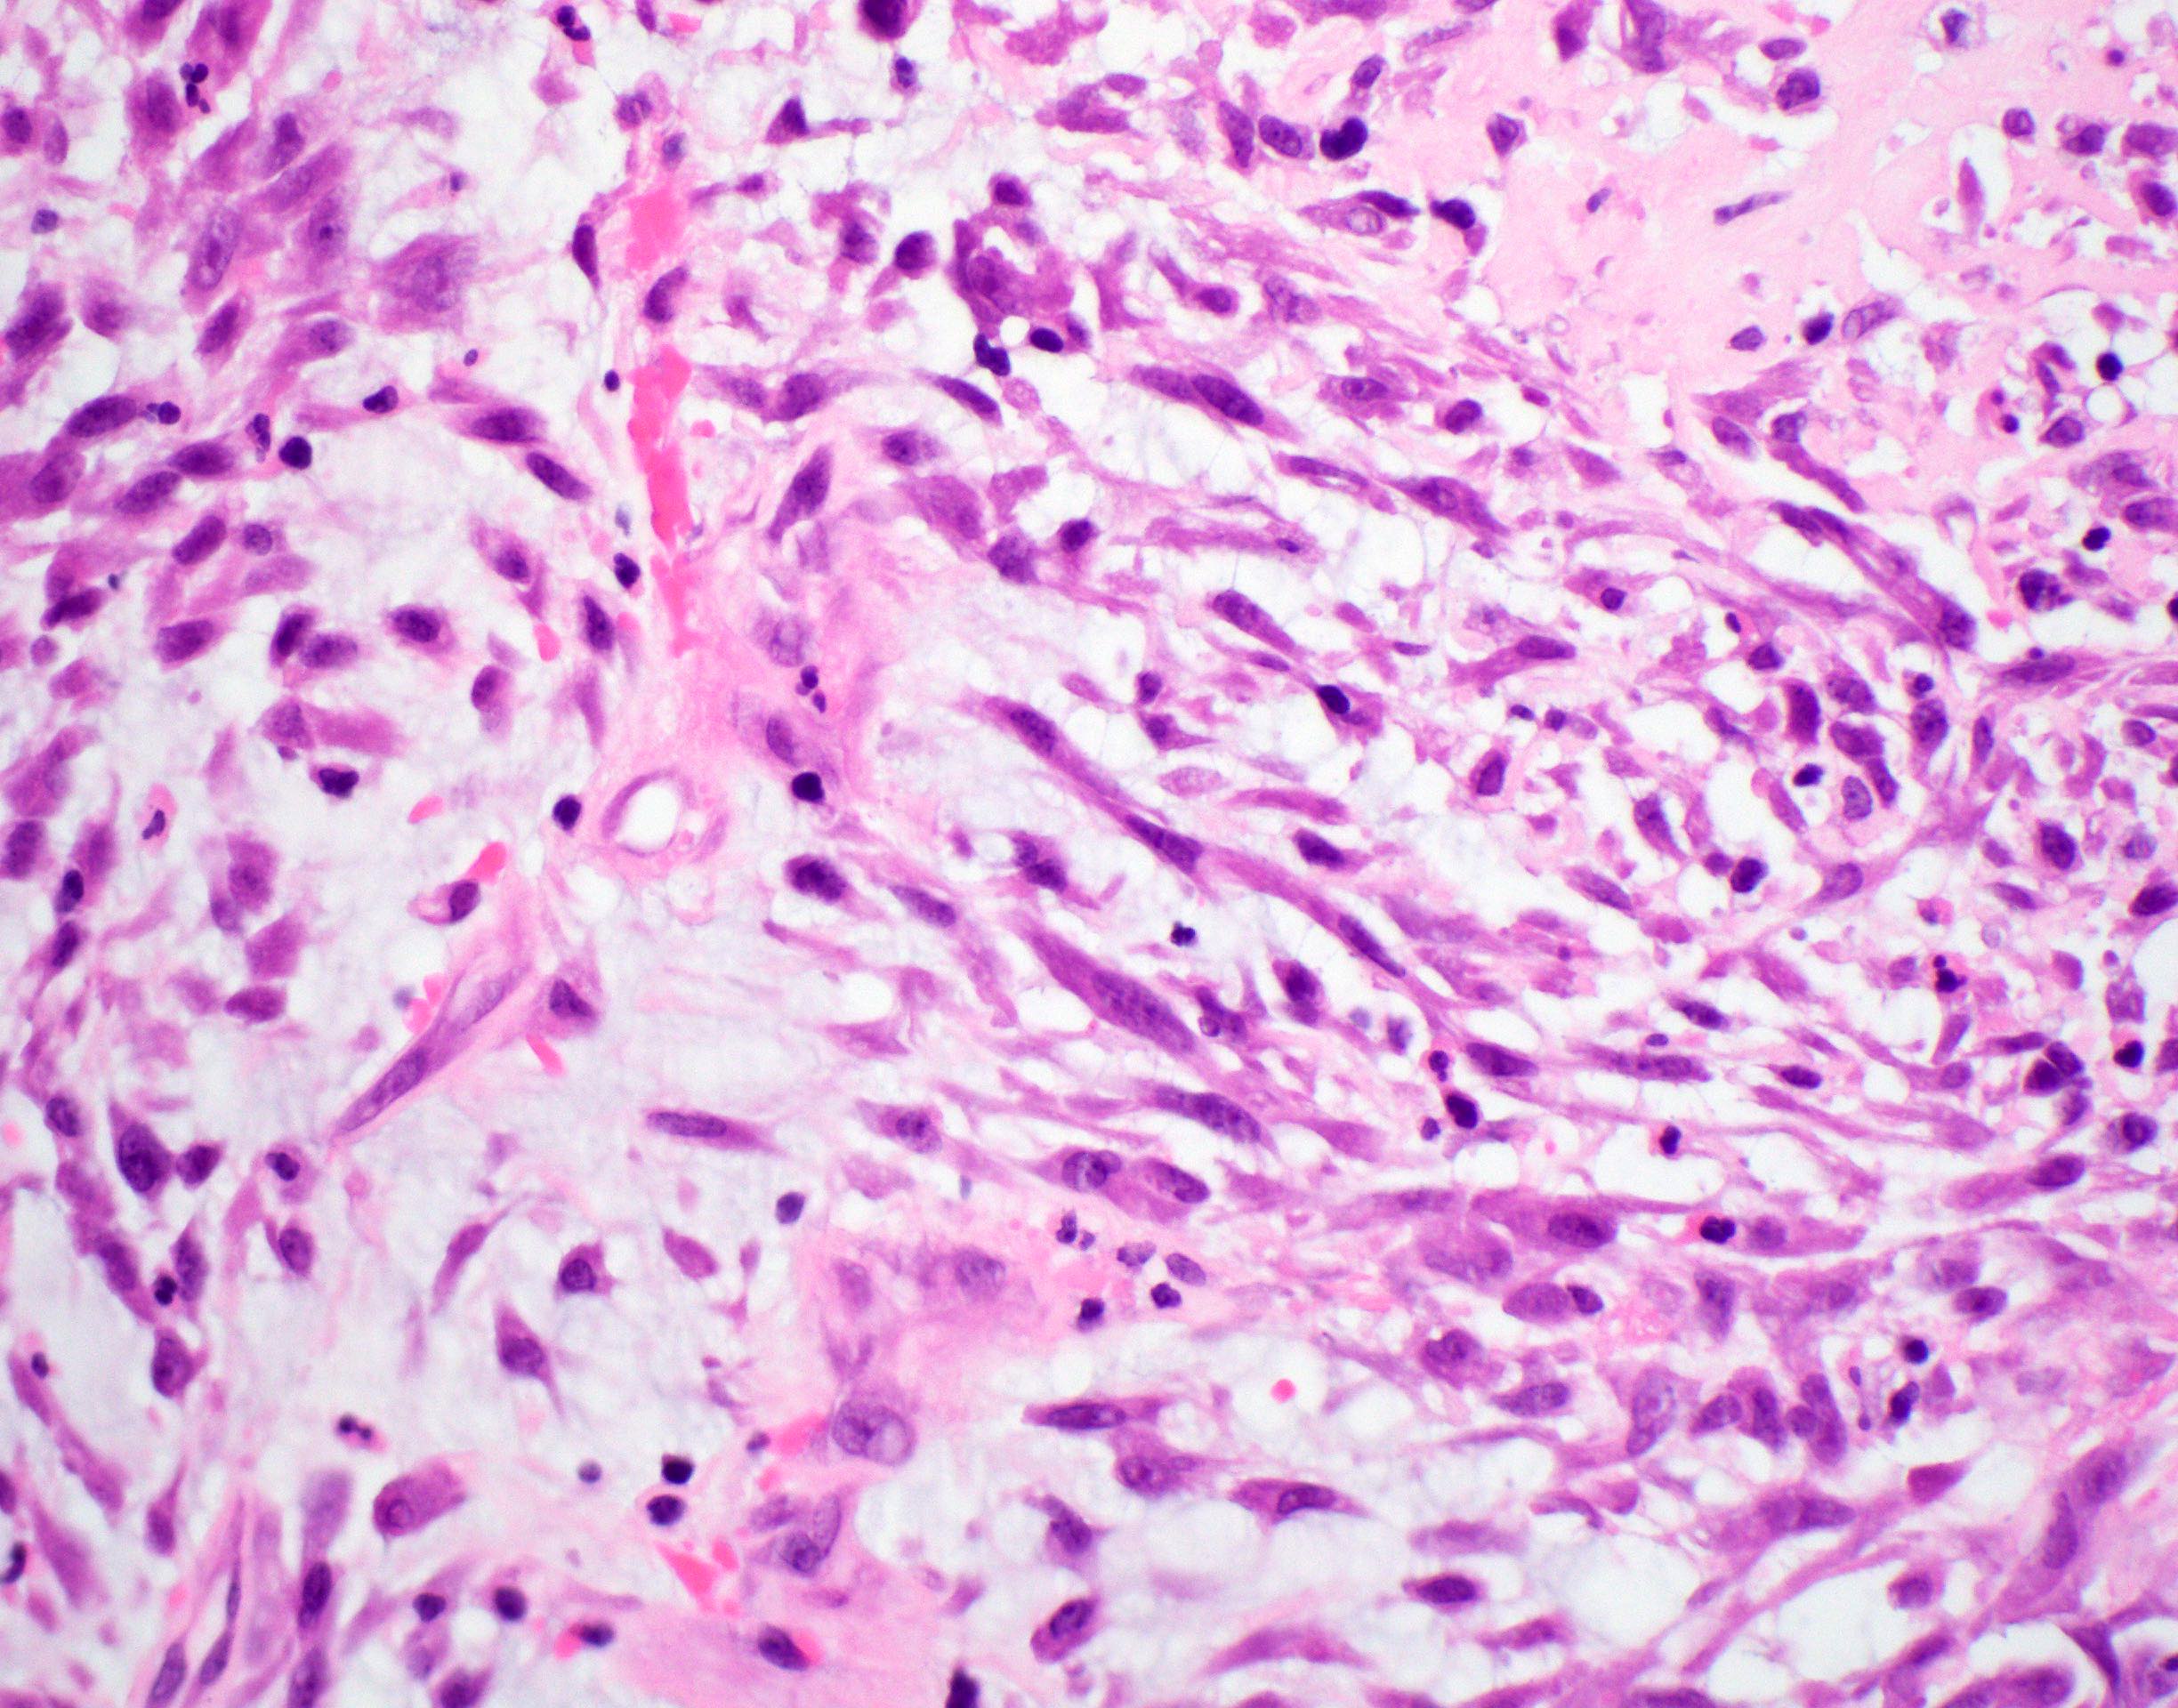

- Spindle cell / sarcomatoid squamous cell carcinoma (Am J Otolaryngol 2008;29:123)

- Most commonly occurs postradiotherapy or as second primary

- Mesenchymal in appearance

- Atypical plump spindled cells arranged in fascicles or storiform pattern

- May have metaplastic or neoplastic cartilage or bone